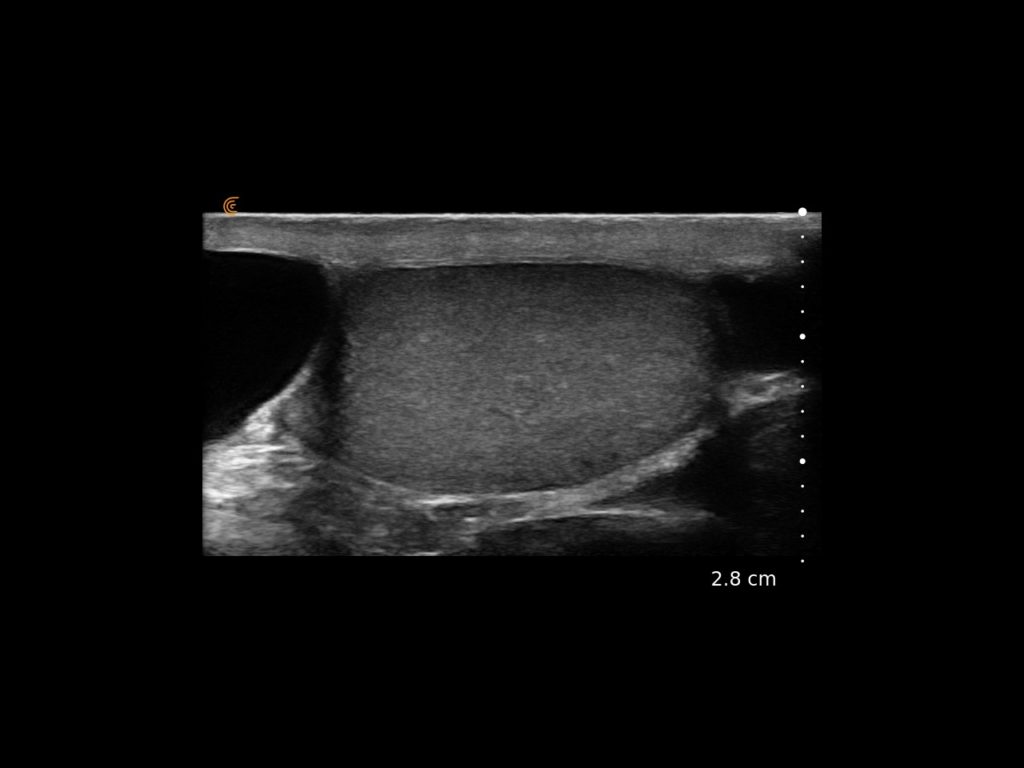

Clarius wireless ultrasound is the ideal system for your office or hospital practice with accurate, high-definition imaging readily available for diagnosis and therapy.

It’s the handheld ultrasound that is going to become the new stethoscope of the 21st century.”